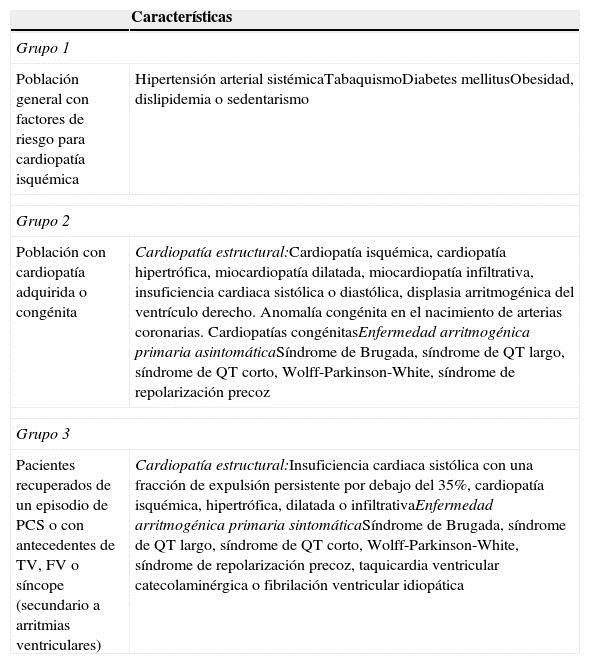

La mayoría de los casos de muerte súbita son pacientes con factores de riesgo para cardiopatía isquémica, sin diagnóstico de enfermedad cardiovascular1-8,29,41; el segundo grupo son los portadores de alguna cardiopatía, pacientes que pueden estar recibiendo atención médica pero que no tienen características de alto riesgo para muerte arritmica6,9-13,16,23; y el tercer grupo son los supervivientes de un paro cardiaco súbito o los que se han detectado con alto riesgo para muerte arrítmica6,25-27,31. En la Tabla 2 se describen las características generales de los 3 grupos de riesgo de muerte súbita cardiaca.

Tabla 2 Grupos de riesgo para muerte súbita cardiaca

FV: fibrilación ventricular; PCS: paro cardiaco súbito; TV: taquicardia ventricular.

Cualquier paciente en estos grupos se considera de mayor riesgo y deberá ser motivo de una revisión más exhaustiva cuando tenga antecedentes familiares de muerte súbita.